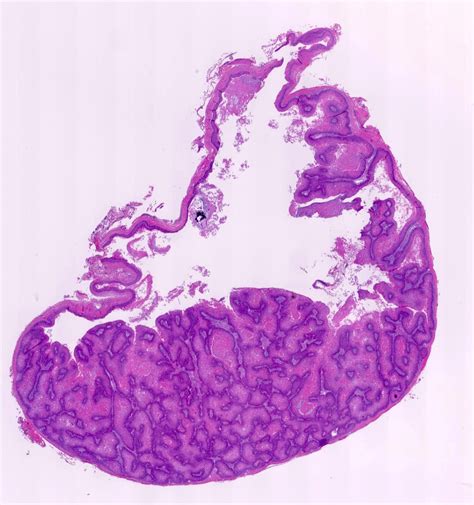

Identifying Trichilemmal Cysts Through Images

Trichilemmal cyst images are invaluable for identifying and diagnosing these cysts. These images can help healthcare providers and individuals recognize the characteristic appearance of trichilemmal cysts. Key features to look for in trichilemmal cyst images include:

• A well-defined, round or oval lump under the skin.

• A smooth, shiny surface that may be skin-colored or slightly yellowish.

• No visible opening or pore on the surface of the cyst.

• In some cases, the cyst may appear red or inflamed if infected.

Below is an example of what trichilemmal cyst images might look like:

Trichilemmal Cyst Images